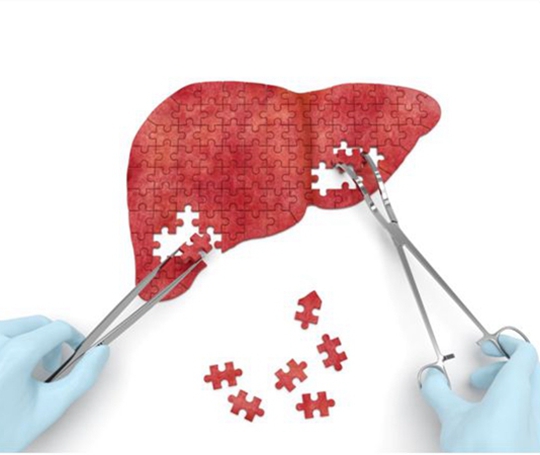

肝癌发病率高,出国治疗肝癌有哪些方法?

肝癌发病率高,出国治疗肝癌有哪些方法?